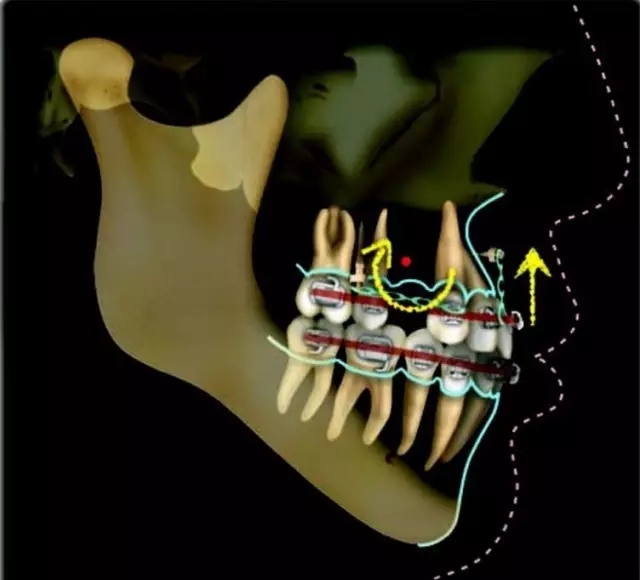

Damon 病例分享:安氏 II 類二分類露齦笑的矯治(董一磊)